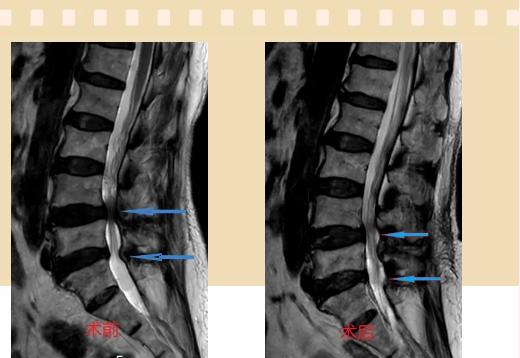

入院后李鵬副主任醫(yī)師為其進行了詳細的查體,完善了術前的檢查,明確診斷為:腰椎管狹窄癥(L4/5、L5/S1),病人合并2型糖尿病,請內分泌科會診,穩(wěn)定血糖后,麻醉科會診病人,排除手術禁忌,李鵬為病人制定了手術方案:單側入路雙側減壓(ULBD)。

手術采用三個微創(chuàng)小切口,兩個節(jié)段減壓手術時間2.5小時,出血50ml。術后2天腰圍保護下床活動,術后5天順利出院。

傳統(tǒng)腰椎管狹窄癥的手術治療,往往需要切開減壓,同時需要內固定融合術,創(chuàng)傷很大,同時可能需要輸血,臥床時間較長,病人合并糖尿病,感染風險也高,而本次采用的UBE-ULBD手術切口更小(加起來約3cm,如果是單節(jié)段狹窄只需要不到2cm切口)、創(chuàng)傷更小,術后恢復較快,可以更早地恢復正?;顒印?/div>

此外,手術保留了病變節(jié)段的穩(wěn)定性,是一種微創(chuàng)的椎管減壓手術,能通過切除部分椎板、關節(jié)突關節(jié)、黃韌帶來解除神經(jīng)根和硬膜囊的壓迫,不需要額外行腰椎內固定術,不需要螺釘及融合器的植入,病人術后腰椎的活動度不受影響。(盧 闖 劉 旭 袁錦鈺)